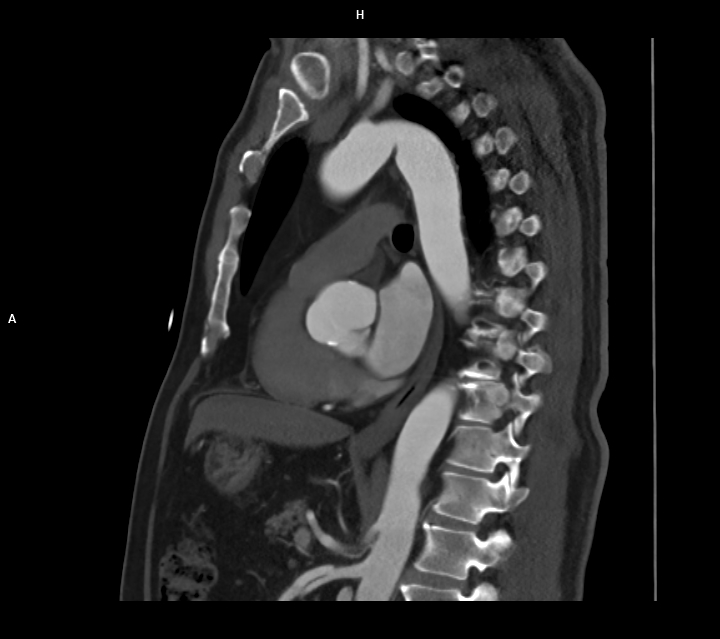

Figura 1: reconstrucție oblic sagitală MIP (maximum intensity projection) din achiziție angioCT torace și abdomen superior cu evidențierea disecției de arteră mezenterică superioară cu ambele lumene circulante

Discuţie caz nr 128: Valva aortică este bicuspidă prin coaptarea cuspei pentru sinusul Valsalva drept și cuspei pentru sinusul non-coronarian, la nivelul cooptării fiind prezenta o calcificare. Secundar valvei aortice bicuspide se remarca creștere de calibru a aortei ascendente, acesta fiind și motivul îndrumării pacientului la examinare CT de aortă toracică – examinare care ar trebui sa fie efectuată obligatoriu cu sincronizare ECG. Întâmplător, la limita inferioară a câmpului de scanare, la nivelul arterei mezenterice superioare se evidențiază un fald de disecție cu ambele lumene circulante.